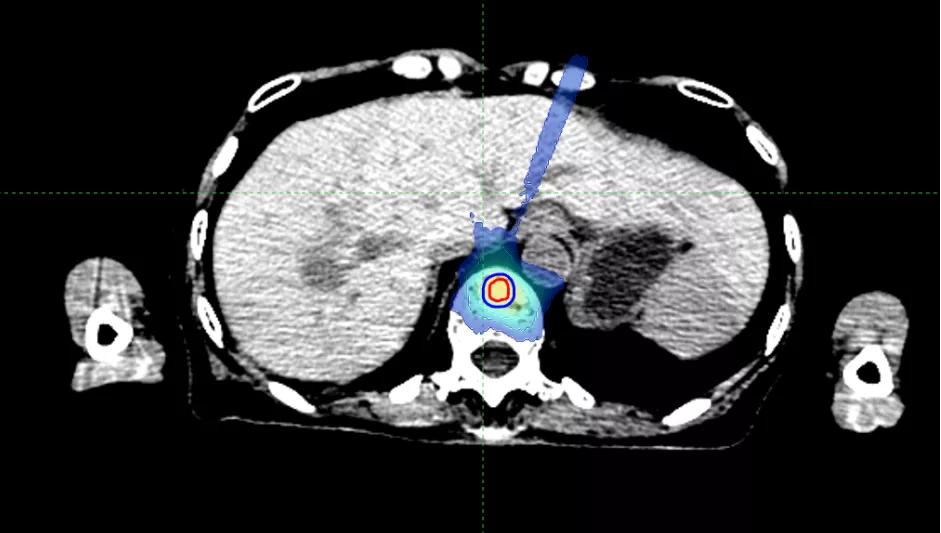

乳腺癌脊柱骨转移,病灶离脊髓很近,射波刀为她开了一扇希望之窗

66岁的罗女士,2019年6月进行左乳腺切除,术后病理报告为浸润性导管癌,三阴性,2019年7月开始为期6周期的化疗。

2021年3月检查发现,T7椎体及T9椎体左侧椎弓根骨质破坏伴FDG代谢增高,考虑骨转移,伴T7椎体病理性骨折。同月做了胸椎融合术+脊柱肿瘤切除人工椎体置换术。2021年4月开始,化疗4周期。2021年9月检查发现,T9-11转移性肿瘤较前增大。

据罗女士的主管医师周霞副主任医师介绍,因T9病灶靠近脊髓附近,如果常规放疗,很可能会造成脊髓不可逆的损伤。于是慕名来到国科大肿瘤医院,胸部放疗科周霞副主任医师为她量身制定了放疗计划,近期开始进行射波刀放射治疗。

周霞介绍,脊柱骨转移瘤是射波刀的拿手好戏。脊髓往往对近在咫尺的脊柱骨转移瘤避无可避,而精准的照射在给它温柔的保护之余,高剂量射线痛击骨内病灶,可以达到缓解疼痛、控制肿瘤的目的。

PGTV1(T9)

PGTV2(T11)